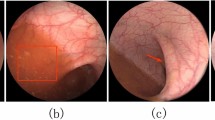

Precise segmentation of intestinal wall vessels is vital to colonic perforation prevention. However, there are interferences such as gastric juice in the vessel image of the intestinal wall, especially vessels and the mucosal folds are difficult to distinguish, which easily lead to mis-segmentation. In addition, the insufficient feature extraction of intricate vessel structures may leave out information of tiny vessels that result in rupture. To overcome these challenges, an effective network is proposed for segmentation of intestinal wall vessels.

A global context attention network (GCA-Net) that employs a multi-scale fusion attention (MFA) module is proposed to adaptively integrate local and global context information to improve the distinguishability of mucosal folds and vessels, more importantly, the ability to capture tiny vessels. Also, a parallel decoder is used to introduce a contour loss function to solve the blurry and noisy blood vessel boundaries.

A novel network for segmentation of intestinal wall vessels is developed, which can suppress interferences in intestinal wall vessel images, improve the discernibility of blood vessels and mucosal folds, enhance vessel boundaries, and capture tiny vessels. Comprehensive experiments prove that the proposed GCA-Net can accurately segment the intestinal wall vessels.